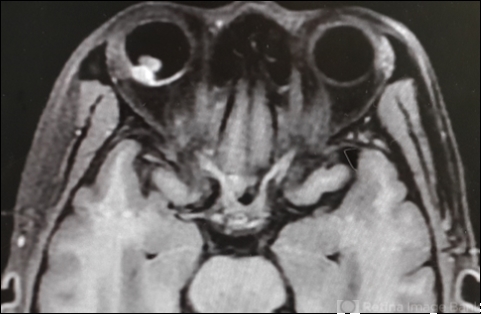

- chorioidal melanoma

- MRI

- MRI-W1 image of a 52-year-old man with a choriod melanoma.